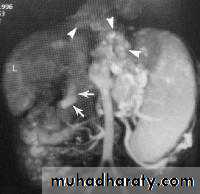

Hypertrophic pyloric stenosisCause:A. Congenital typeB. Adult type

Epidemiology:-

Pyloric stenosis is relatively common and has a male predilection (M:F ~ 4:1), and is more commonly seen in Caucasians 4.

It typically occurs between the 4-8 weeks of life. There may be a positive family history.

Incidence of hypertrophic pyloric stenosis is approximately 2-5 per 1,000 births per year in most white populations.

In a normal situation, the pyloric muscle thickness (diameter of a single muscular wall on a transverse image) should normally be less than 3 mm (most accurate 3) and the length (longitudinal measurement) should not exceed 15 mm.